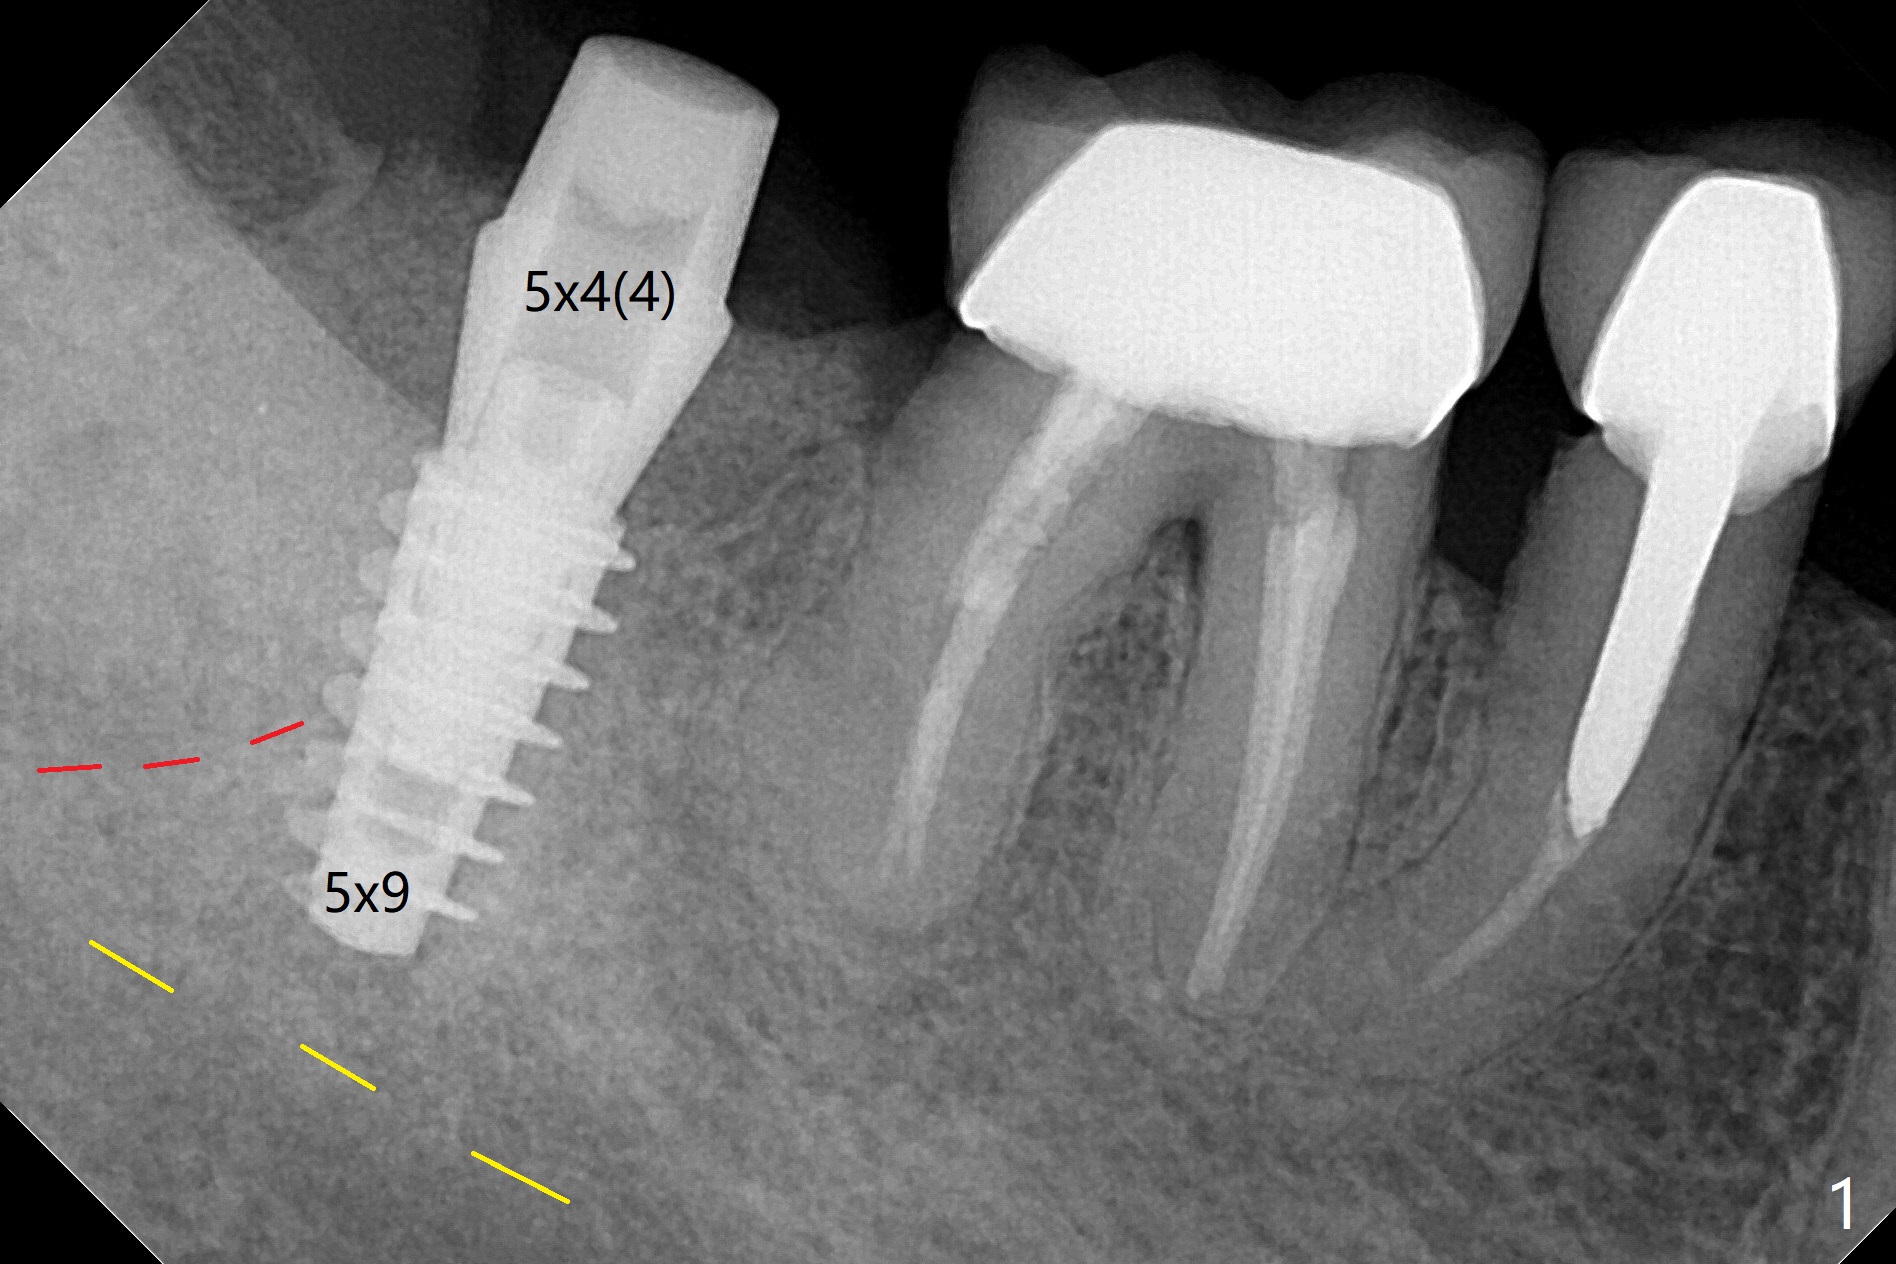

31号牙拔牙后根尖肉芽组织多,病人怕痛,局麻药用的多,而且需要阻滞。不过在导板帮助下,植体还是种在牙槽窝近中斜坡上(图一:红虚线(黄虚线(下齿槽管)))。